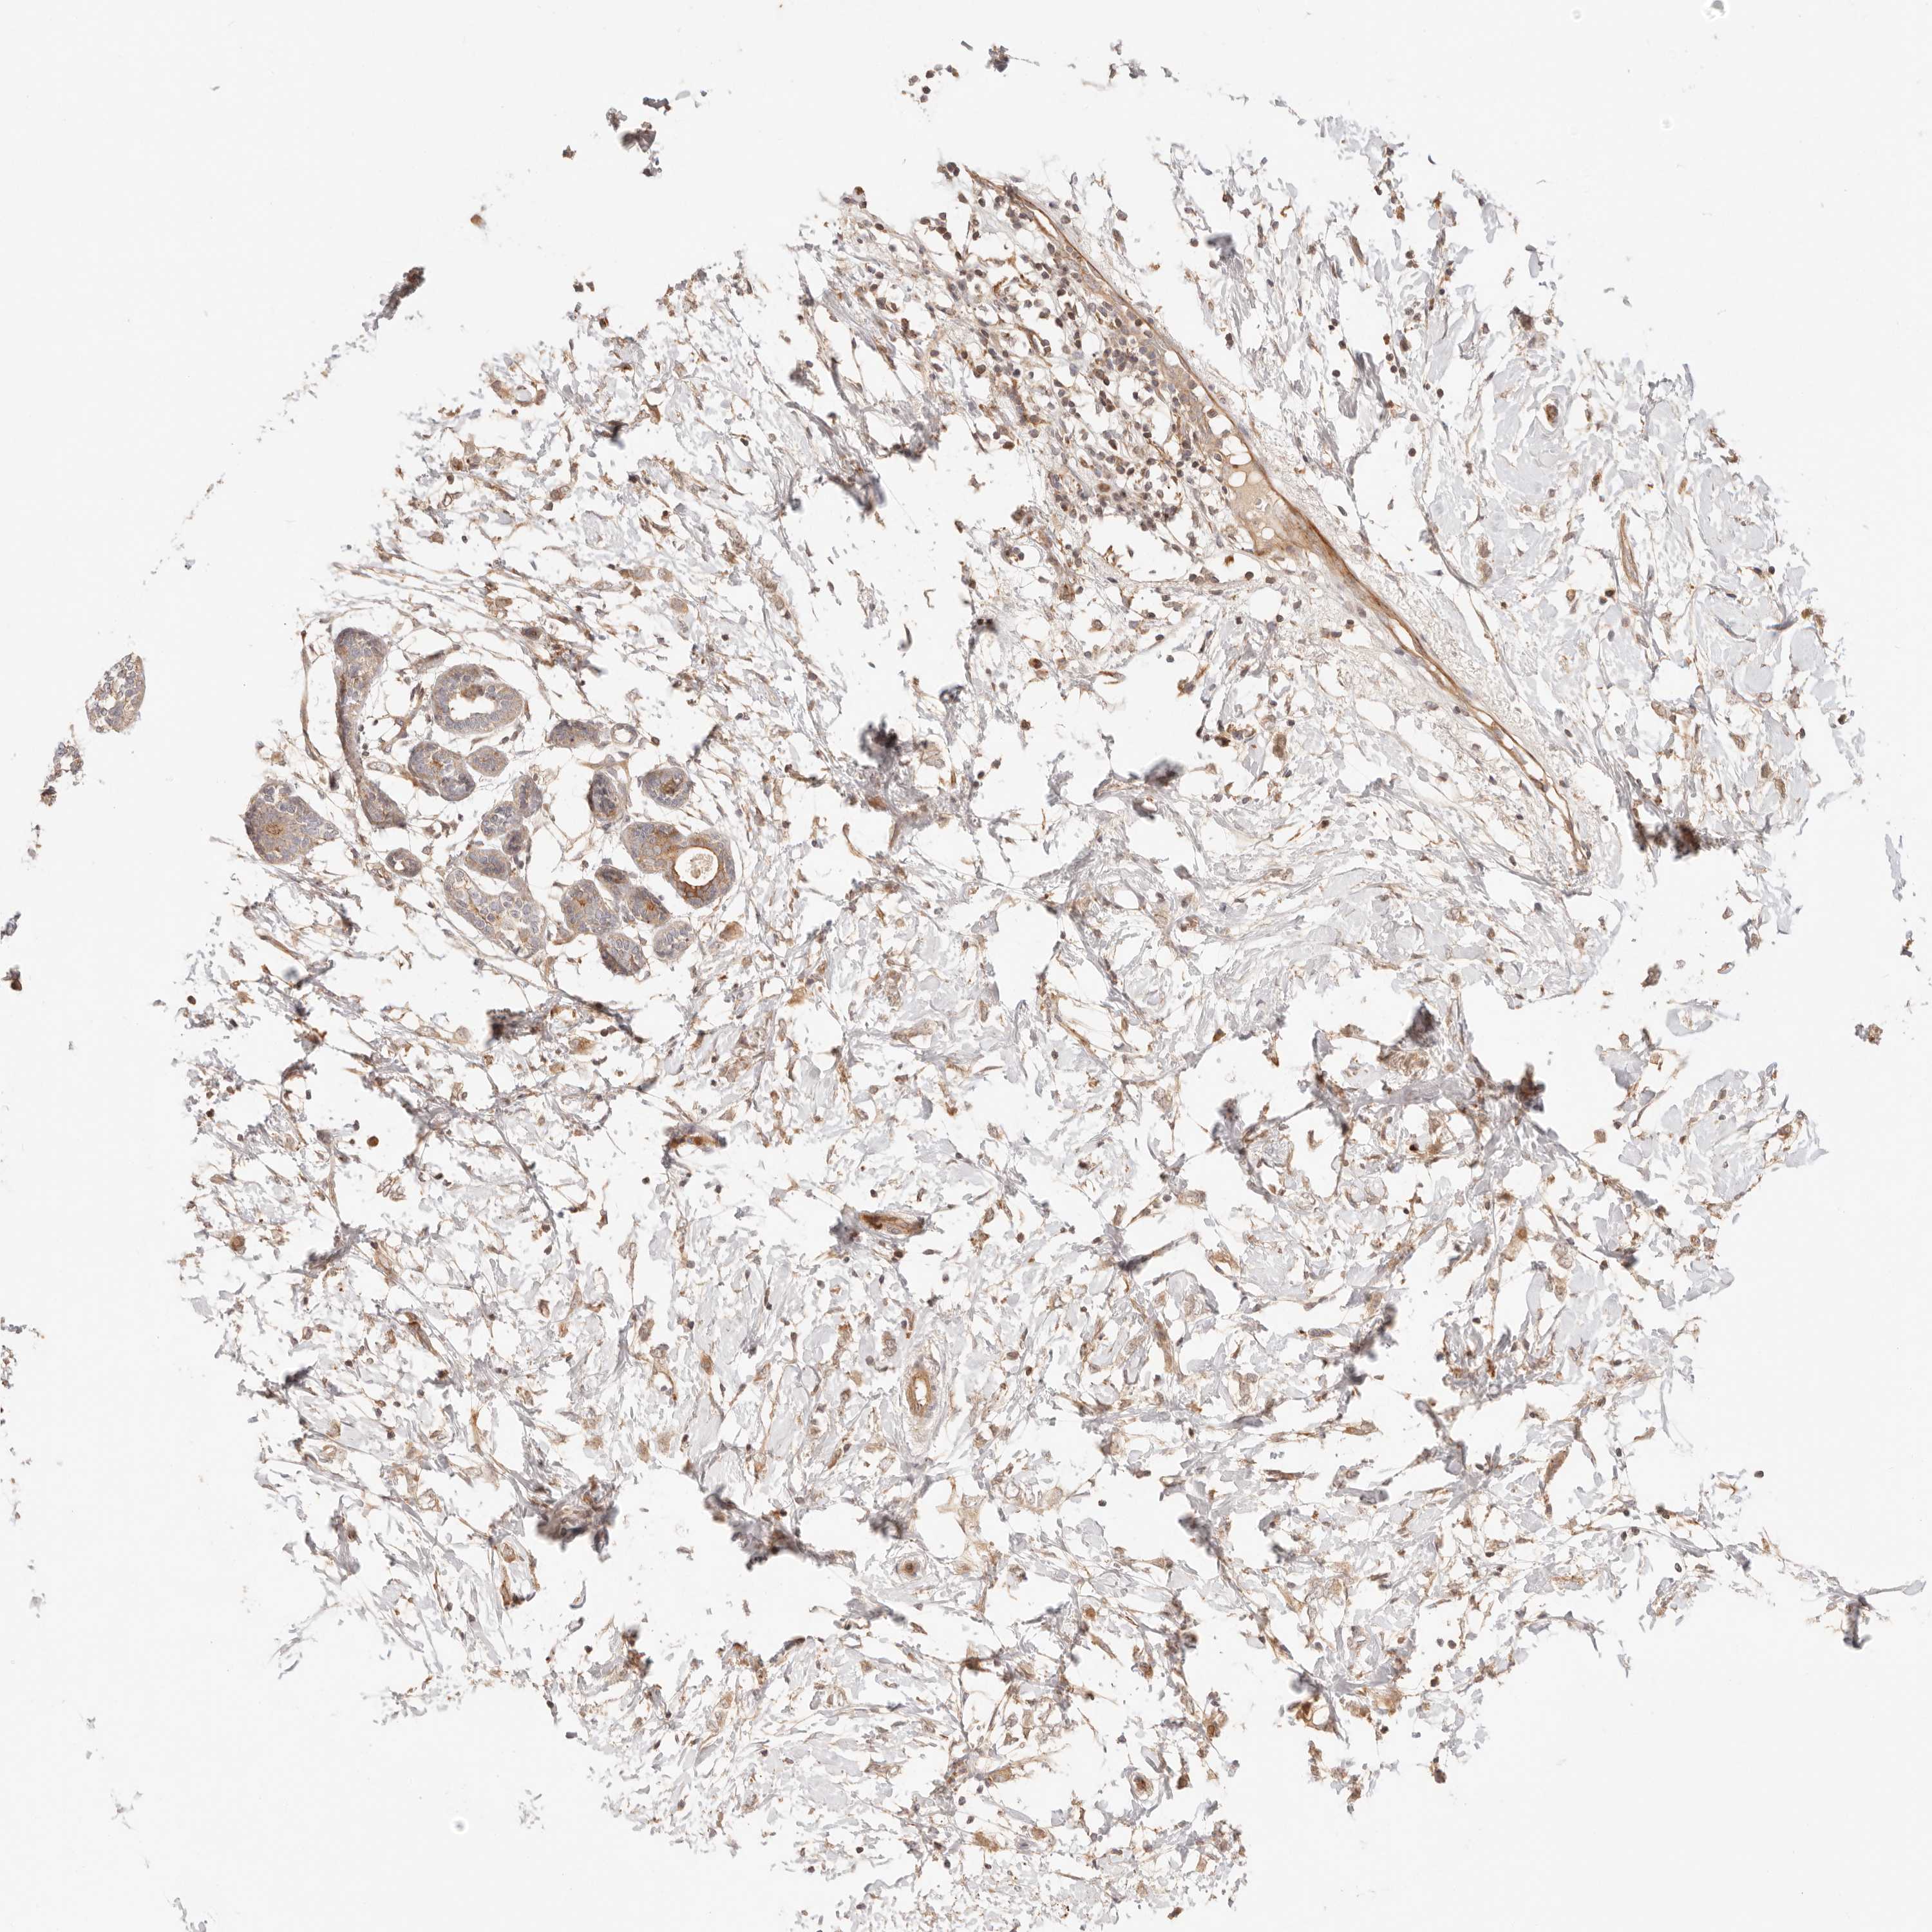

BRCA TCGA BRCA VALIDATION PROTEIN EXPRESSION